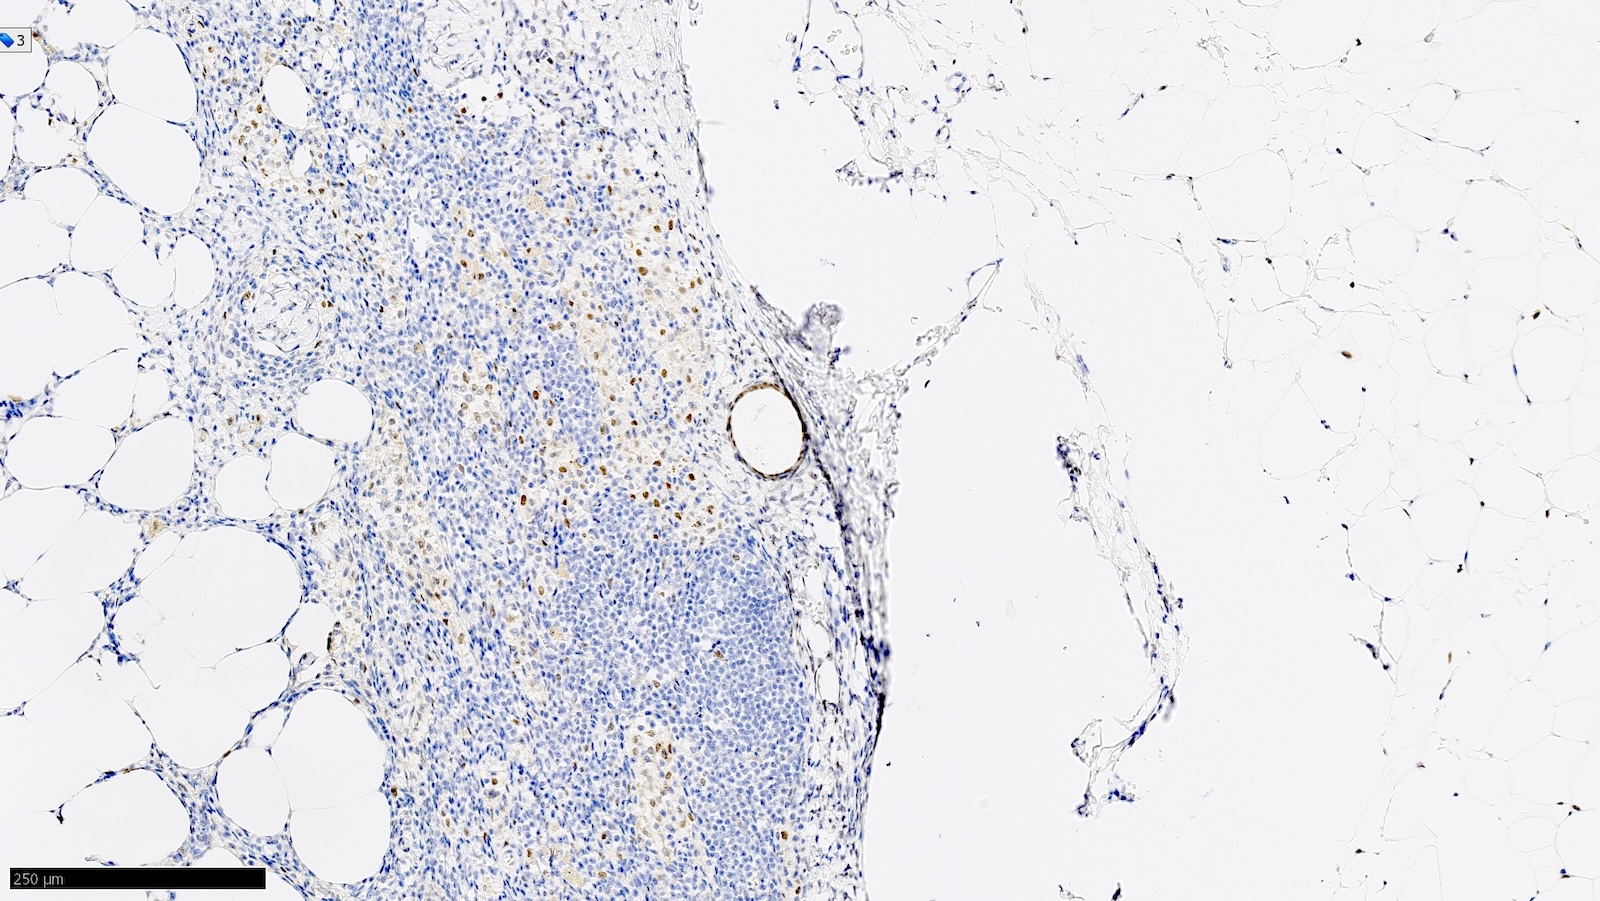

Microscopic (histologic) images

Contributed by Sucheta Srivastava, M.D., Jaya Ruth Asirvatham, M.B.B.S., Rahul Koshy, D.O. and Julie M. Jorns, M.D. (Case #548)

Positive stains

- Note: "enhanced methods" of SLN metastasis detection, including routine immunohistochemistry, are not recommended (i.e. should be used on a case by case basis / when necessary for diagnosis) (J Clin Oncol 2014;32:1365)

- AE1 / AE3, CK7, GATA3

- Estrogen receptor / ER (depends on biomarker status)

- Reference: Semin Diagn Pathol 2018;35:143